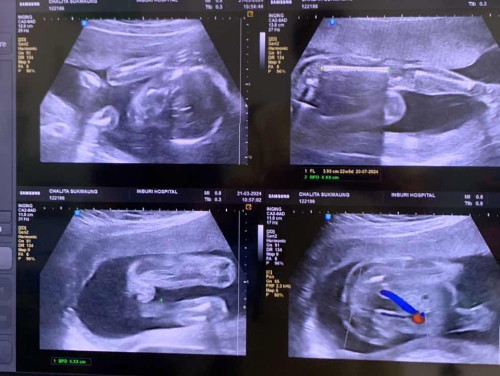

ลูกสาวคนแรก🥰👨👩👧 พ่อชื่อเอฟ แม่ชื่อชมพู่ค่ะ กำหนดคลอด 24 ก.ค.